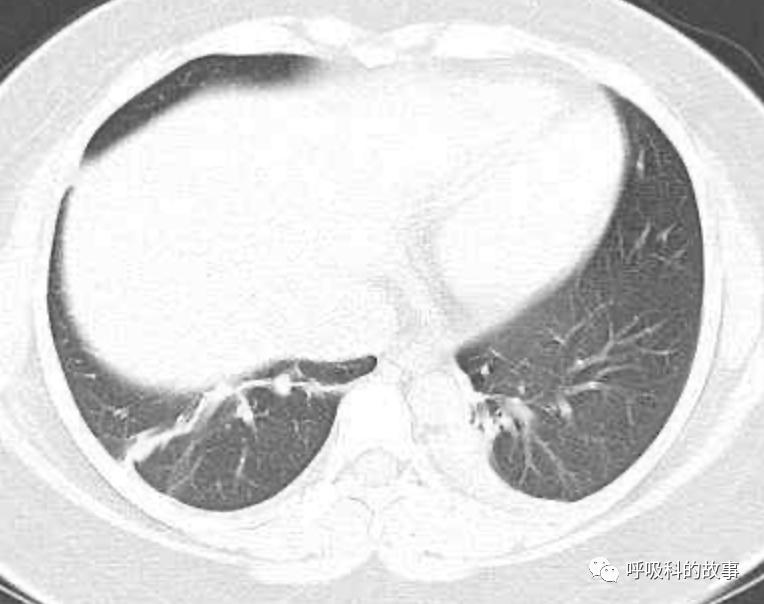

患者发热后行胸部CT检查(6月21日,住院第13天),可见两下肺有条片影,当时考虑是肺炎引起的发热。